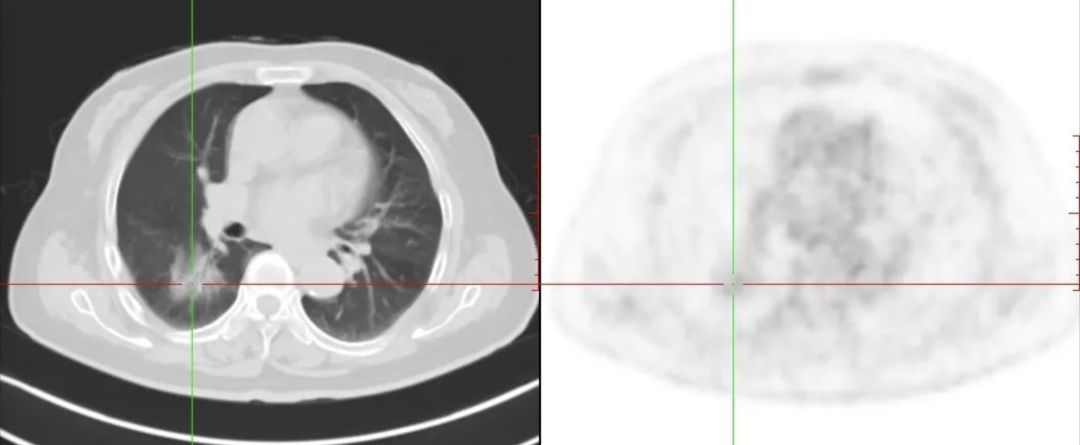

“恶性肿瘤”来,“良性病变”出,青滨附院PET/CT告诉您原因何在